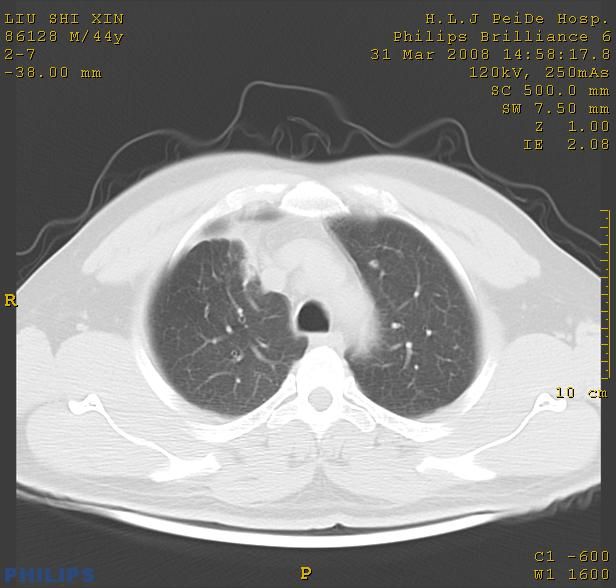

标题: CT13096:请分析胸膜下结节的影像基础是什么 有病理结果 [打印本页]

标题: CT13096:请分析胸膜下结节的影像基础是什么 有病理结果

考虑右上叶慢性炎症可能性大,不完全除外肺癌。

瘢痕挛缩,胸膜牵拉,血管纠集扭曲,上叶前段支气管显示欠清,周围散在斑片影,以纵隔旁肺癌可能性大。请穿刺检查。

中心型肺癌并阻塞性肺炎及肺内转移

中心型肺癌并阻塞性肺炎、两肺及胸膜多发转移。

本病例有病理结果是,鳞状上皮癌,胸膜下结节影病现诊断的肿大淋巴结,谢谢大家分析,请问胸膜下结节是肿大淋巴结怎么解释